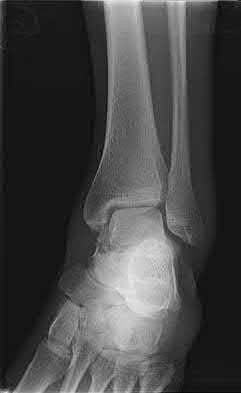

2. # A 35-year-old woman is involved in a head-on collision while driving. Initial radiographs are shown in Figures 8a and 8b. Injury to what vessel increases the risk for osteonecrosis of the injured bone?

5. Artery of the tarsal sinus Corrent answer: 4

The patient has a Hawkins type III talar neck fracture-dislocation with a risk of osteonecrosis ranging from 69% to 100%. Anatomic studies have shown that the artery of the tarsal canal supplies the lateral two thirds of the talar body.

The other vessels listed provide no significant contribution to the talus.